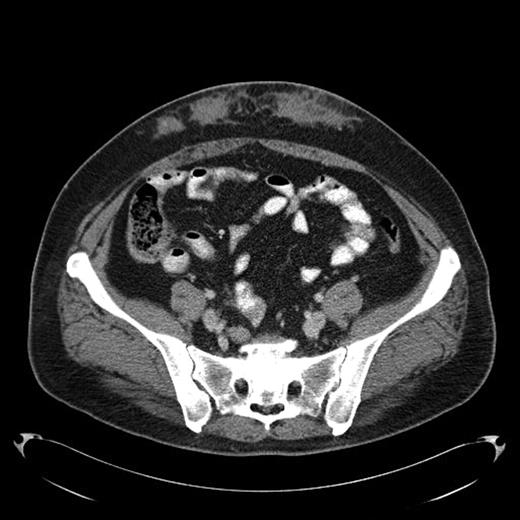

A 43-year-old female diagnosed with diabetes mellitus in 1986 after acute pancreatitis secondary to hypertriglyceridemia presented to our hospital in December of 2008 with a 2 year history of low grade fever of 99-100F. This was associated with chills and fatigue. Over the same time period she had noticed anterior abdominal wall nodularity, particularly at sites where she has been injecting her insulin. Her insulin requirement had also increased from a total of 60 units of NPH in a day to 170 units per day. Because of the subcutaneous nodularity at the site of injection a decision was made to switch the site of the insulin which resulted in lower blood glucose level and subsequently significant decrease in her insulin requirement to 120 units a day. This suggested poor absorption from the infiltrated site. At our clinic laboratory data showed normal white count of 5.4 × 10(9)/L with normal differential, normal hemoglobin of 12.9 g/dL with an ESR of 11 mm/hour, creatinine of 0.8 mg/dL and C-reactive protein of less than 3. As part of the work up for fever of unknown origin a CT-scan of the abdomen was obtained which showed infiltrative lesion in the anterior abdominal subcutaneous tissue with few calcifications Fig 1 & 2. Biopsy of the anterior abdominal wall nodular infiltrate was performed. Tissue cultures came out negative for infection. The biopsy showed eosinophilic material positive with Congo red staining and showing apple green birefringence when viewed under polarized light. Immunohistochemical staining showed this to be negative for AA, AL, or TTR amyloidosis. Liquid chromatography tandem mass spectrometry (LC MS/MS) detected peptides representing apolipoprotein E, apolipoprotein A-IV, SAP and Insulin. The amyloid deposits stained positive with anti-insulin. The presence of peptides from insulin and immunohistochemical reactivity with an anti-insulin antibody indicated that the amyloid deposits were caused by insulin injection at this site. Work up for systemic amyloidosis including serum protein electrophoresis with immunofixation was negative for a monoclonal protein. Quantitative immunoglobulins were within normal range. Her 24-hour urine protein was 65 mg within normal range. Her serum free light chains were unremarkable. Echocardiogram did not show any evidence of infiltrative cardiomyopathy. This was therefore consistent with localized insulin induced cutaneous amyloidosis. The recommendation was to change the insulin type and to rotate the insulin injection site. Because of occasional hemorrhage and pain the long term plan will be to surgically remove the amyloid deposits.

Amyloid infiltration in subcutaneous tissue of lower abdomen at insulin injection site